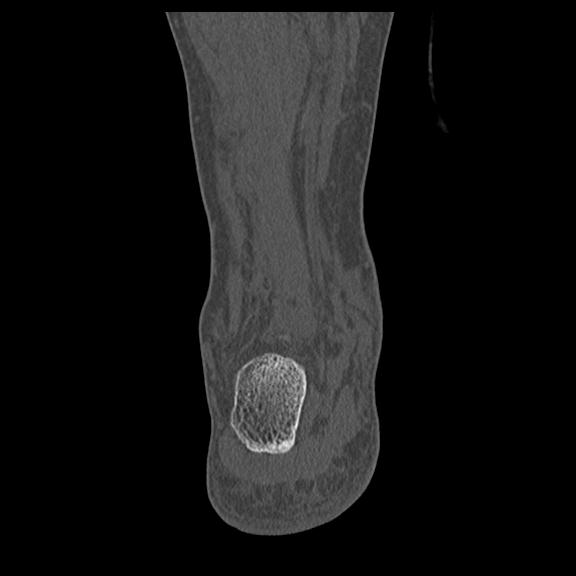

56476 8/28 4R 1/21 2R 左足関節 デジカメ写真 72歳女性 右足関節AS